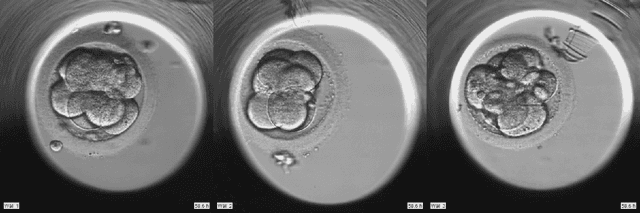

Abstract:To optimize clinical outcomes, fertility clinics must strategically select which embryos to transfer. Common selection heuristics are formulas expressed in terms of the durations required to reach various developmental milestones, quantities historically annotated manually by experienced embryologists based on time-lapse EmbryoScope videos. We propose a new method for automatic embryo staging that exploits several sources of structure in this time-lapse data. First, noting that in each image the embryo occupies a small subregion, we jointly train a region proposal network with the downstream classifier to isolate the embryo. Notably, because we lack ground-truth bounding boxes, our we weakly supervise the region proposal network optimizing its parameters via reinforcement learning to improve the downstream classifier's loss. Moreover, noting that embryos reaching the blastocyst stage progress monotonically through earlier stages, we develop a dynamic-programming-based decoder that post-processes our predictions to select the most likely monotonic sequence of developmental stages. Our methods outperform vanilla residual networks and rival the best numbers in contemporary papers, as measured by both per-frame accuracy and transition prediction error, despite operating on smaller data than many.